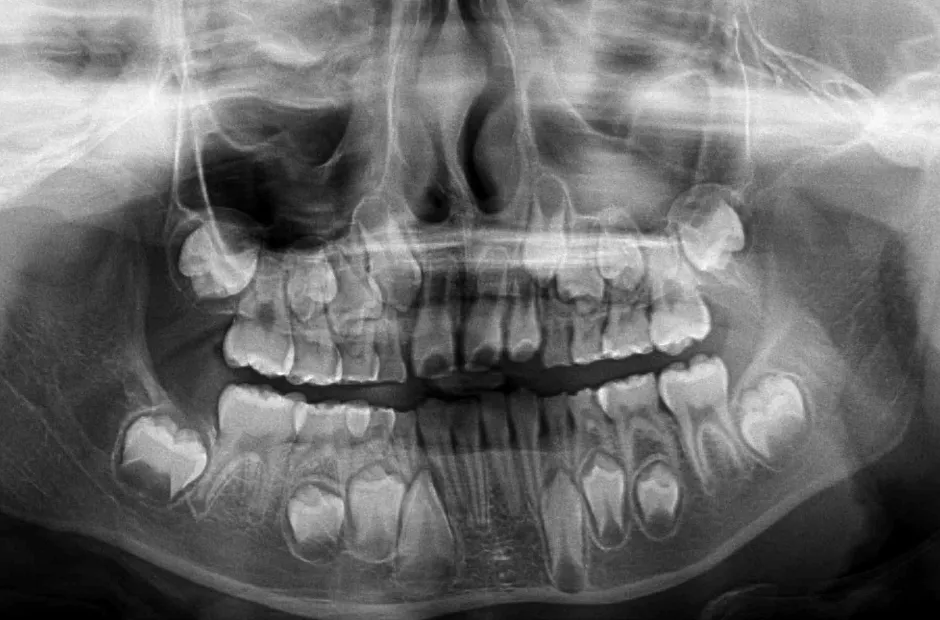

口腔内写真やレントゲンの撮影、歯型取りなど、口や顎の状態を詳しく把握するための精密検査を行ないます。さらに、骨の成長状況や身長・体重の増加傾向、永久歯の生えかわりについても確認します。

先天的な歯や顎の症状

永久歯が生えてこない(埋伏歯)

何らかの原因で永久歯が正常に生えることができず、歯肉に埋もれたままになる歯のことを埋伏歯といいます。この歯を放置すると、隣の歯根を吸収してしまうことがあるため、早めの治療が必要です。埋伏歯を早期に発見できると、抜歯せずに矯正治療で正常な位置に戻せる可能性が高くなります。これは、小児矯正では、顎の成長を促進して歯が正しく並ぶスペースを作ることができるからです。そのため、乳歯が永久歯に生え変わり始めるころに一度受診し、埋伏歯の有無を確認することが大切です。

歯が多い(過剰歯)

通常、永久歯は親知らずを含めて32本ありますが、過剰歯とはその数を超えて余分に歯が生えている状態を指します。過剰歯が歯肉の中に埋まっていて、向きが悪くほかの歯に害を及ぼしている場合には抜歯が必要です。しかし、問題がなければそのまま経過を見守ることもあります。